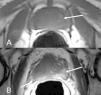

Los criterios utilizados en la RM para considerar que el tumor prostático tiene extensión extracapsular incluyen7,51 (fig. 8): protrusión focal irregular espiculada de la cápsula , pérdida de la hiposeñal normal de la cápsula, obliteración del ángulo rectoprostático, asimetría y afectación del plexo neurovascular y extensión del tumor a las vesículas seminales (tabla 3). La invasión de la vesícula seminal se demuestra por la presencia de hiposeñal en el seno de las vesículas51. Se ha demostrado útil la utilización de la secuencia de difusión como criterio de infiltración de la vesícula seminal46 (fig. 9). Para obtener la máxima eficacia en la estadificación del cáncer de próstata en RM es imprescindible utilizar una bobina endorrectal o multicanal de pelvis con el fin de obtener estudios de alta resolución de la pelvis11.

Criterios en la RM de extensión extracapsular. A) Protrusión focal irregular, espiculada de la cápsula (flecha). B) Obliteración del ángulo rectoprostático (flecha). C) Afectación y asimetría del plexo neurovascular y grasa periprostática (flecha). D) Extensión a la vesícula seminal izquierda (flecha).

Es importante conocer que después de la biopsia pueden observarse irregularidad de la cápsula (fig. 10)13, sin que ello sea indicativo de extensión capsular, o artefactos postbiopsia. Por ejemplo, en un estudio la eficacia de la estadificación local disminuyó del 83% al 46% debido al artefacto postbiopsia en la RM52. Es difícil valorar de forma objetiva los resultados publicados sobre la fiabilidad de la RM en la estadificación local del cáncer de próstata, debido a las distintas técnicas y métodos utilizados. De todas formas, según un meta-análisis realizado sobre 74 estudios publicados en relación a la estadificación del cáncer de próstata se concluye que los mejores resultados se obtienen realizando el examen RM de la próstata con secuencias de alta resolución en múltiples planos utilizando una bobina endorrectal49. El criterio más específico de extensión extracapsular (EEC) es la asimetría del plexo neurovascular (sensibilidad 38%, especificidad 95%) y el más sensible es la valoración global de todos los criterios de EEC (sensibilidad 68%, especificidad 72%)53.